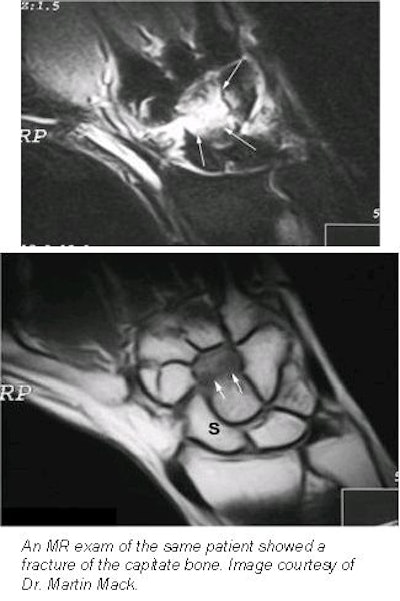

According to a study by Dr. Martin Mack and colleagues at the Johann Wolfgang Goethe-Universtät in Frankfurt/Main, Germany, high-resolution MRI has advantages over conventional film-screen radiographs in the early diagnosis of wrist trauma.

The same evaluation team then reviewed the MRI results and found scaphoid, radius, and other fractures in 20 of the patients, with 36 showing no fracture. There were false-positive results on plain radiographs in more than half of the patients. False-negative diagnoses of the radiographs were found in 6 cases. Between MRI and the radiographs, the diagnostic agreement of the observers was 44.6% and 55.4%, respectively.

In more than a third of the patients, MRI allowed for the detection of additional injuries to soft tissue. Bone bruises were found on 15 patients, discus lesions were observed in 7, and ligament injuries and ligament avulsion were found in 5 and 8 patients, respectively. In addition, 13 patients were diagnosed with joint effusion, and cysts were discovered in 3 patients.